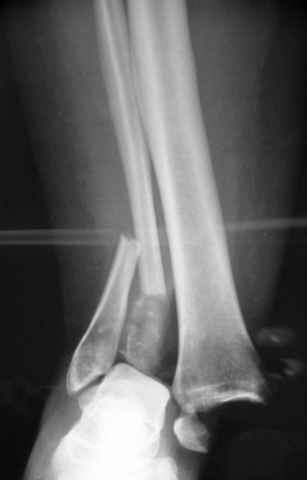

Второй случай сделан из одного разреза

ЕЧ LISS plate, mininvasive approach - luxurous !

На прямой проекции послеоперационного Рг макроскопически все выглядит очень анатомично, при микроскопическом ( :-)) ) рассмотрении можно все-таки заметить вальгизацию тарана, суставная щель в латеральном отделе сустава несколько уже , чем в медиальном при отсутствии латерального смещения тарана. У меня был аналогичный случай (без LISS , без мини доступа) с вальгусным наклоном тарана при восстановленном ankle mortise при последовательном наблюдении с интервалами в 6-8 недель в послеоперационном периоде отмечалось прогрессирующее сужение суставной щели в латеральном отделе сустава, закончившееся посттравматическим ОА, к счастью боли умеренные, купируемые аналгетиками или своими эндорфинами:-))(активная пациентка, у которой нет времени на болезни....) Какова жизненная ситуация в приведенном вами случае? И последнее, что я хотел бы прояснить для себя - фиксация внутренней лодыжки: я обычно комбинирую фиксацию компрессирующим винтом со спицей - по идее ротационная стабильность должна быть лучше, чем один винт, каковы ваши наблюдения в этом плане?